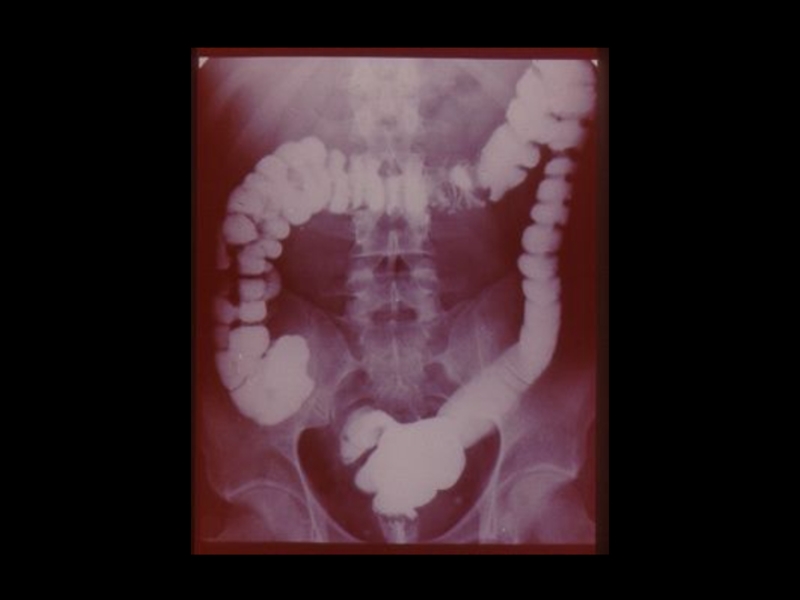

3. Специальные методы

(урография, бронхография, ангиография,

лимфография, пневмоартрография и другие)

Слайд 38Виды рентгеноконтрастных веществ:

I. Негативные - газы

( Воздух,

кислород, углекислый газ, закись азота )

II. Позитивные- соли тяжелых металлов

( Сернокислый барий, производные йода )